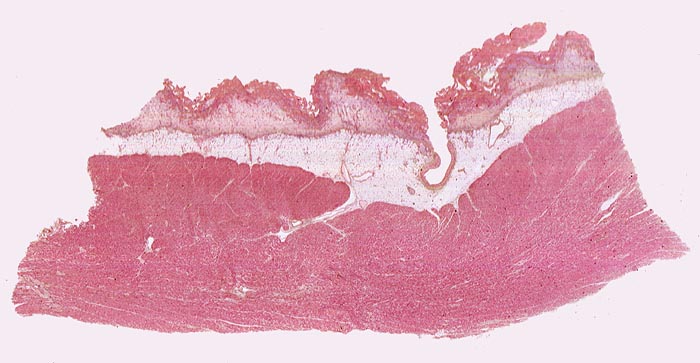

PathoPic – image database / PathoPic ID 4531 - fibrinöse Perikarditis

fibrinöse Perikarditis

Perikard

Das Epikard (innere Schicht des Perikardblattes) ist bedeckt von einer zottigen Fibrinschicht. Gegen innen folgt eine Granulationsgewebsschicht, welche das Fibrin organisiert, gefolgt vom epikardialen Fettgewebe und vom Myokard. Ehemalige Lokalisation der Perikardoberfläche (einschichtiges Mesothel). Koronararterienast im epikardialen Fettgewebe.

Patientin verstorben in Urämie.